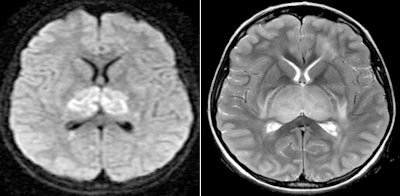

The patient had a normal chest x-ray that was performed when she was admitted to the hospital, as well as a normal-appearing CT exam. However, when an MRI exam was performed 14 hours later, it demonstrated multifocal signal abnormalities. Extensive symmetric restricted diffusion was identified in the thalami bilaterally. Restricted diffusion was also found in the periventricular white matter of the centrum semiovale, medial temporal lobes, and pontine gray nuclei, and symmetrically within the medial cerebellar hemispheres.

In addition, Lyon and colleagues identified an abnormally high T2 signal in areas of restricted diffusion, and more extensively in the brainstem and centrum semiovale.

| Axial diffusion-weighted image (1000b), left, shows restricted diffusion in the thalami bilaterally. Axial T2-weighted image, right, demonstrates enlarged heterogeneous thalami with predominant T2 hyperintensity. All images courtesy of Driscoll Children's Hospital. |